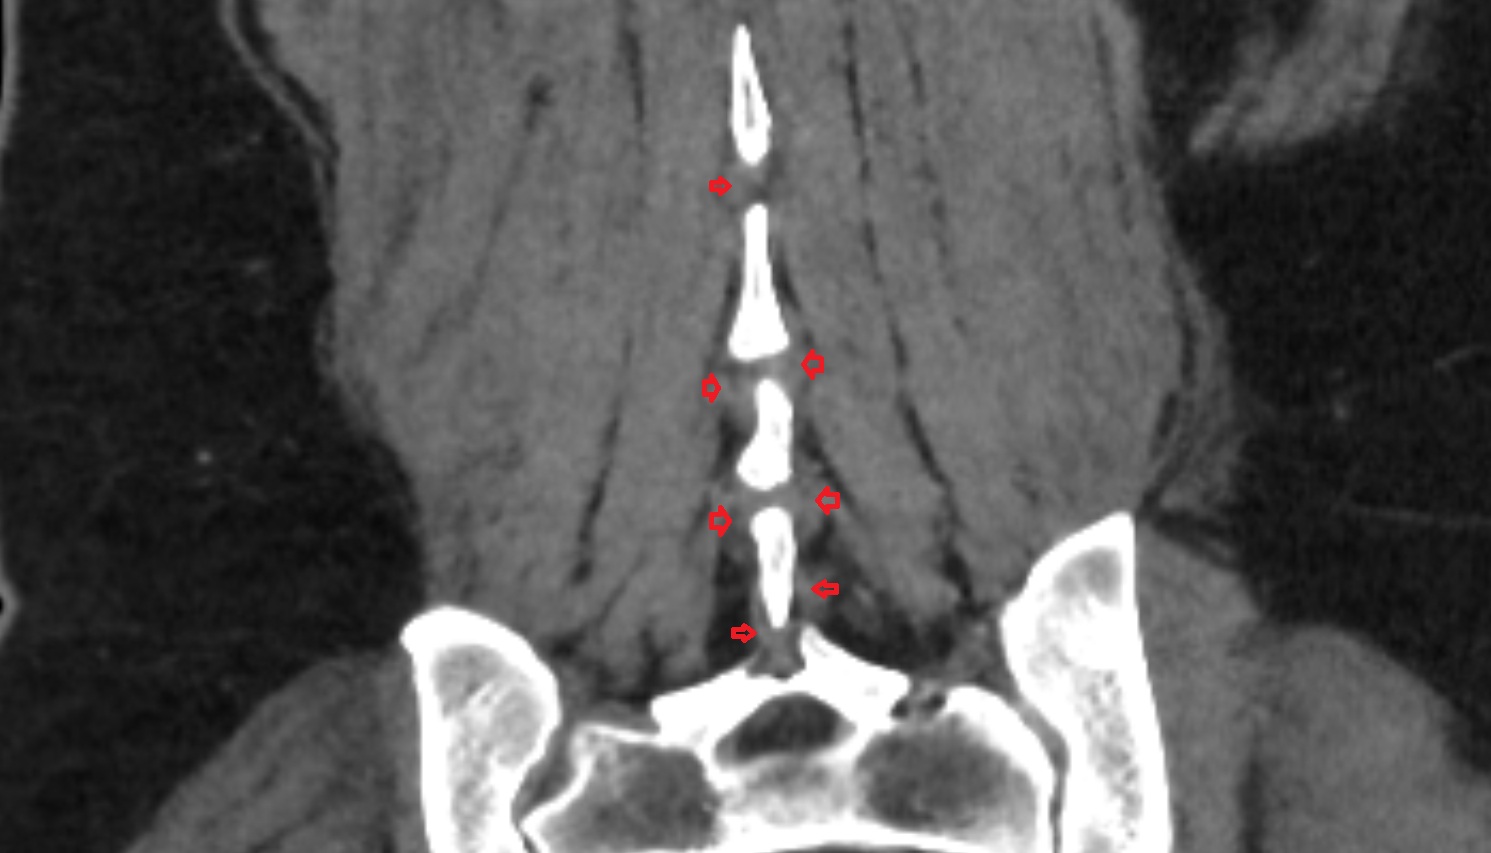

- Cauda equina

- Conus medullaris

- Traversing nerve root of spinal nerve

- Exiting nerve root of spinal nerve

- Exiting nerve root of spinal nerve S1

- Traversing nerve root of spinal nerve S1

- Traversing nerve root of spinal nerve S2

- Traversing nerve root of spinal nerve S3

- Traversing nerve root of spinal nerve S4

- Exiting nerve root of spinal nerve S2

- Exiting nerve root of spinal nerve S3

- Exiting nerve root of spinal nerve S4

- Exiting nerve root of spinal nerve S5

- Filum terminale internum